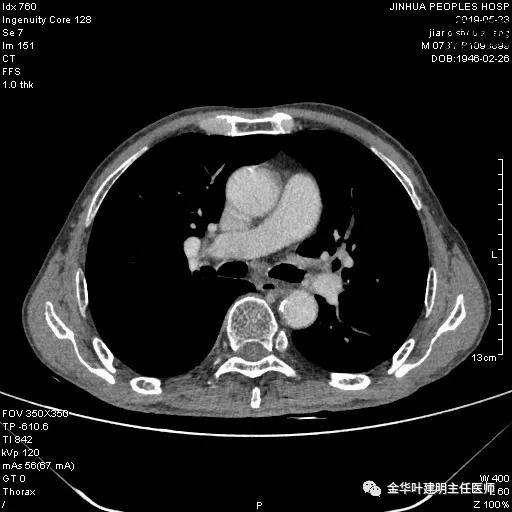

考虑左侧大量胸腔积液,遂进一步胸部CT检查:

以上是肺窗表现,下面为纵隔窗影像: